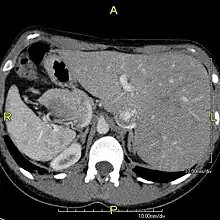

However, in some individuals with PCD, mutations thought to be in the gene coding for the key structural protein left-right dynein (lrd)[4] result in monocilia which do not rotate. There is therefore no flow generated in the node, Shh moves at random within it, and 50% of those affected develop situs inversus, which can occur with or without dextrocardia, where the laterality of the internal organs is the mirror-image of normal. Affected individuals therefore have Kartagener syndrome. This is not the case with some PCD-related genetic mutations: at least 6% of the PCD population have a condition called situs ambiguus or heterotaxy, where organ placement or development is neither typical (situs solitus) nor totally reversed (situs inversus totalis) but is a hybrid of the two.[6] Splenic abnormalities such as polysplenia, asplenia and complex congenital heart defects are more common in individuals with situs ambiguus and PCD, as they are in all individuals with situs ambiguus.[18]